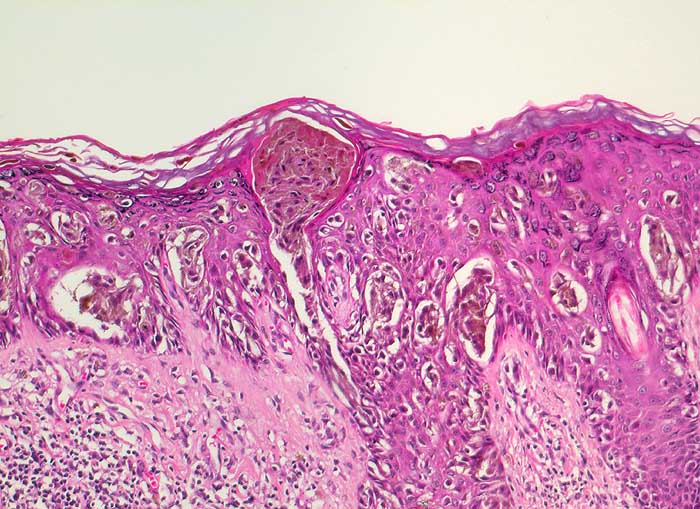

PathoPic – image database / PathoPic ID 6632 - Melanoma in situ

Melanoma in situ

Sehr unterschiedlich grosse und unterschiedlich geformte Nester stark pigmentierter atypischer Melanozyten. Zusätzlich zahlreiche atypische Einzelzellen, die die gesamte Breite der Epidermis durchwandern. Die angrenzende papilläre Dermis ist lymphozytär infiltriert ohne Nachweis von Tumorzellen.

Tumor am Rücken: V.a. auf malignes Melanom DD: dysplastischer Naevus.